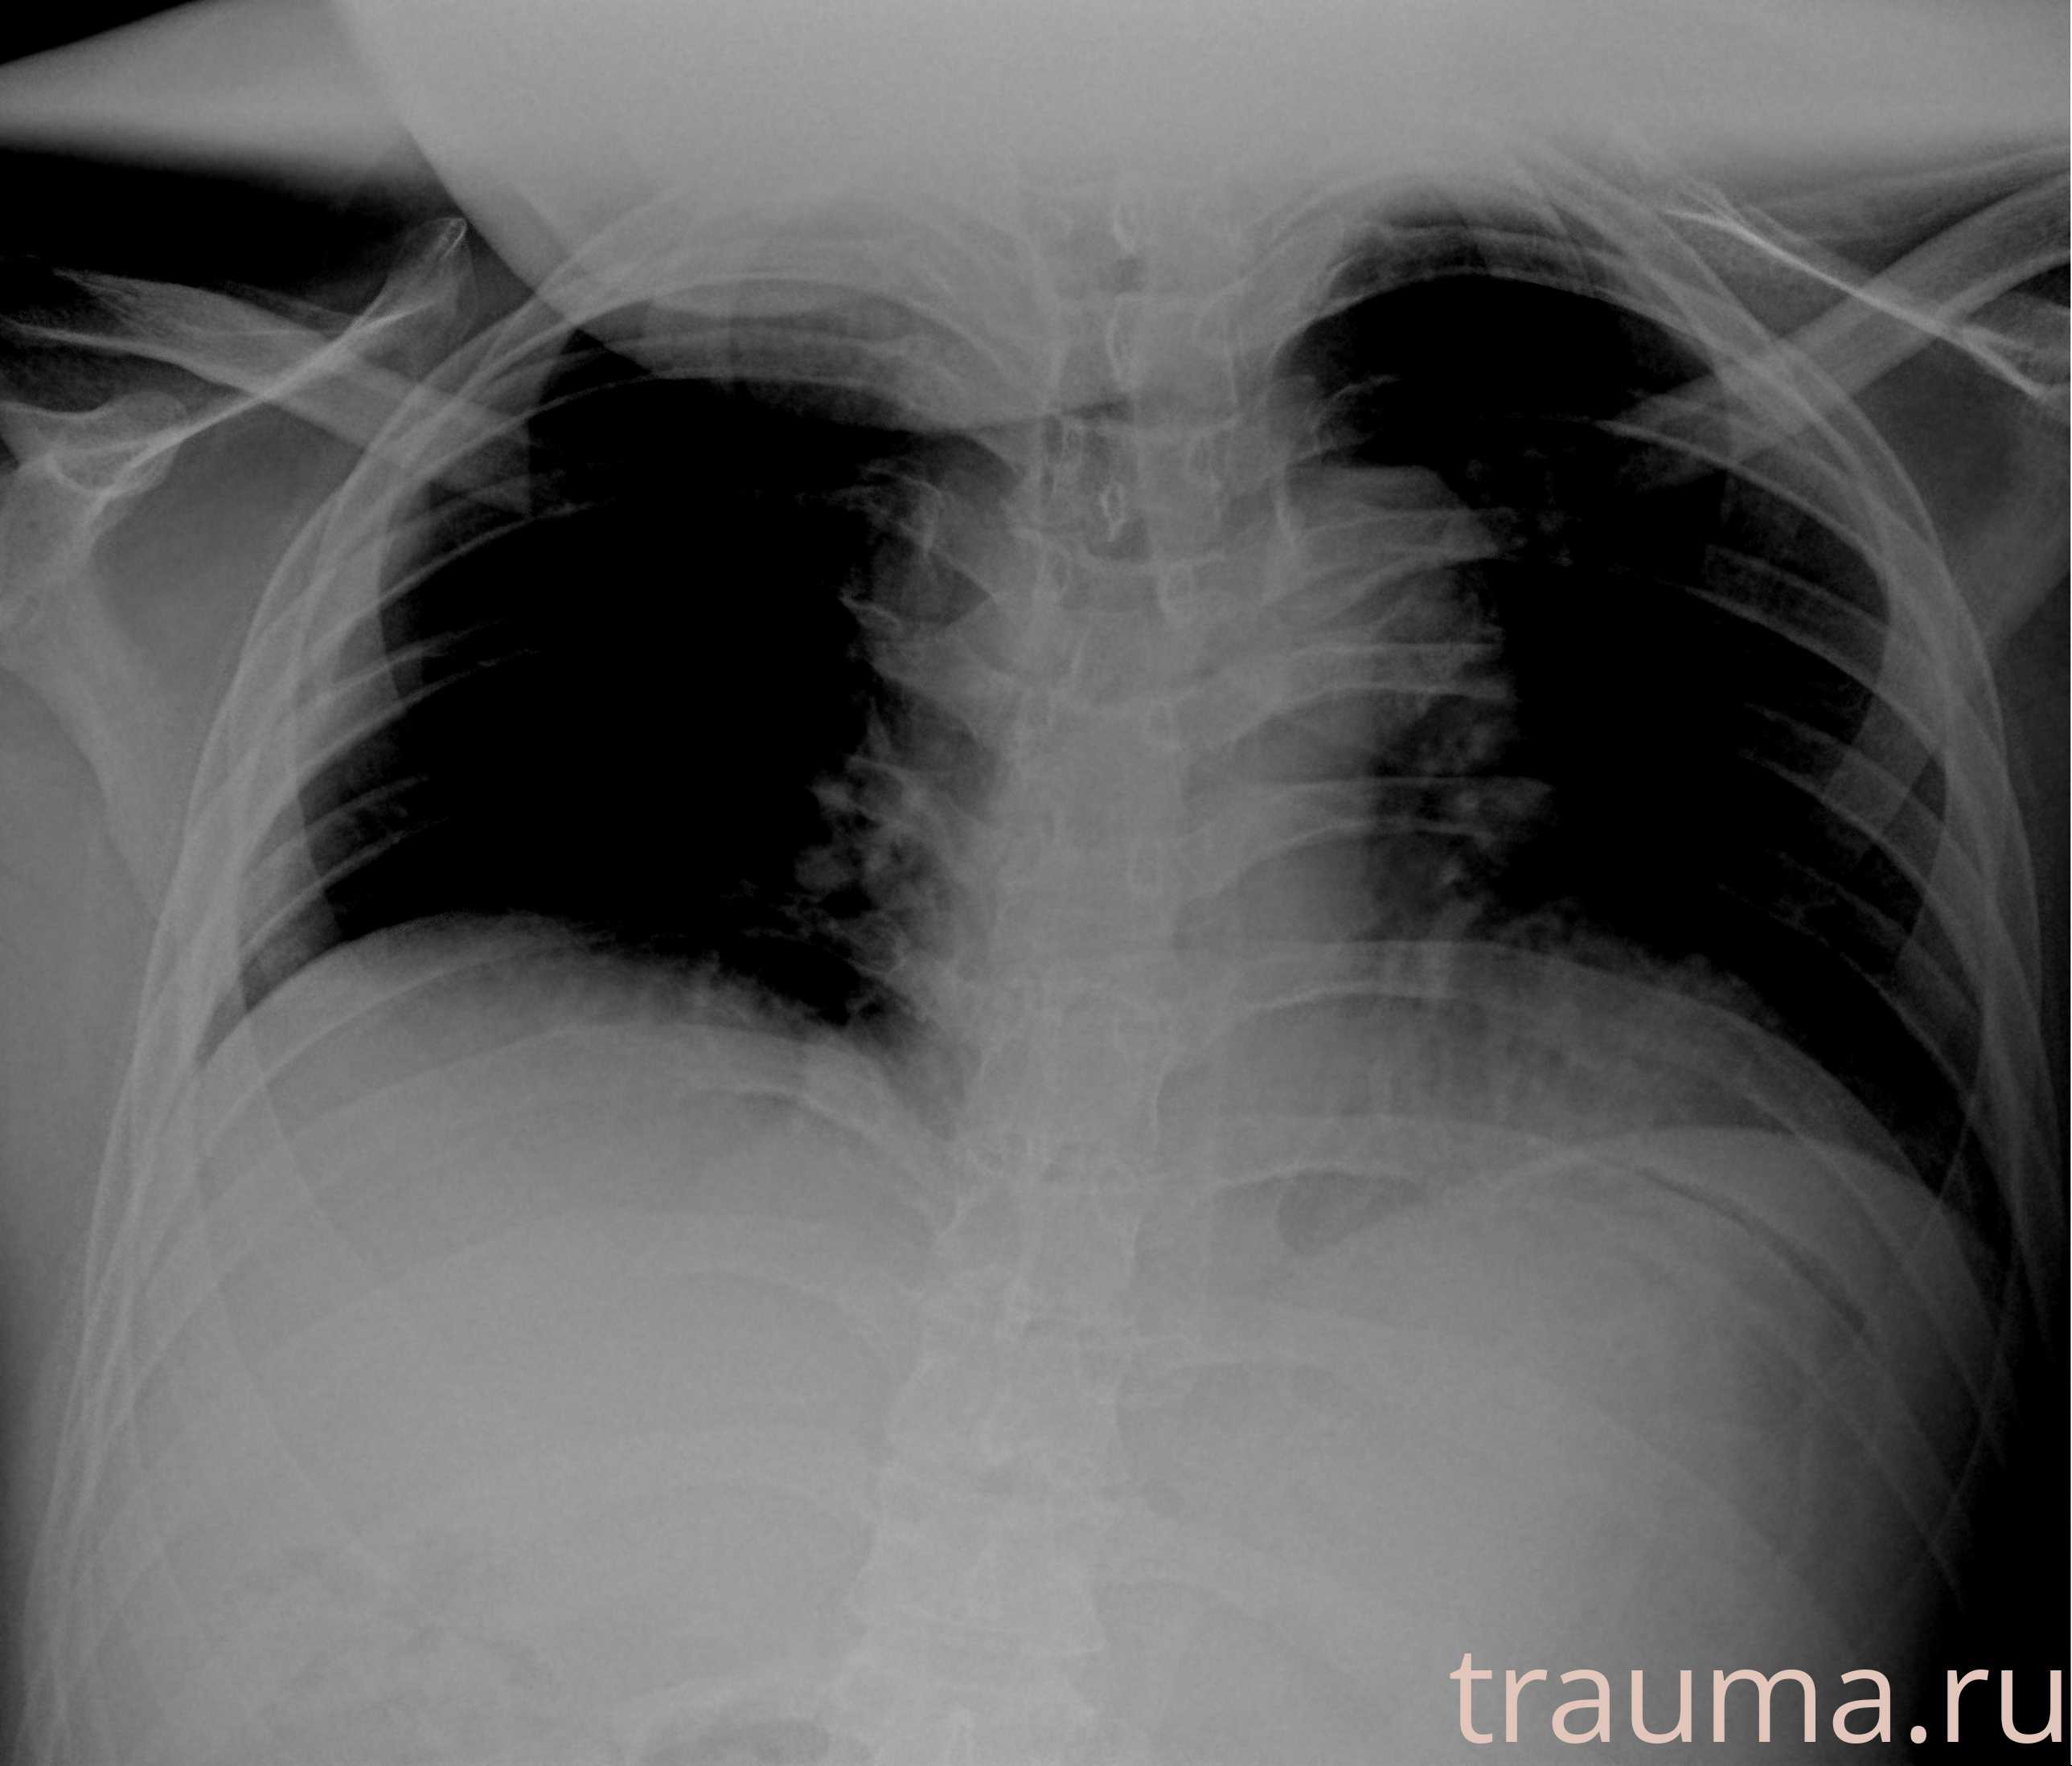

Рентгенограммы

Рентген на дому: по вашему адресу приезжает врач-рентгенолог, травматолог-ортопед с мобильным рентгеновским аппаратом, проводит диагностику травмы или заболевания, делает необходимые рентгенограммы, дает рекомендации по дальнейшему лечению. Получить качественные снимки в домашних условиях возможно благодаря уникальной методике, разработанной МосРентген Центром для института  Склифосовского

при переломе шейки бедра и пневмонии от компании МосРентген Центр - партнера Института имени Склифосовского